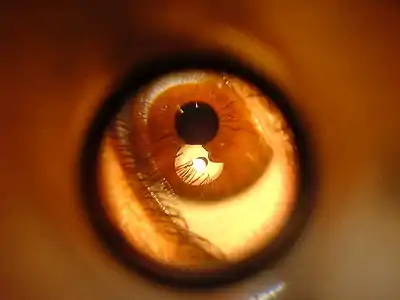

3. Anatomy of the Eye

4. Eye Examination